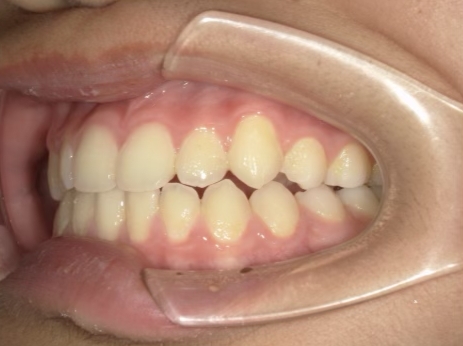

治療中➁ 小3:9y1m

前歯をブラケットで並べる